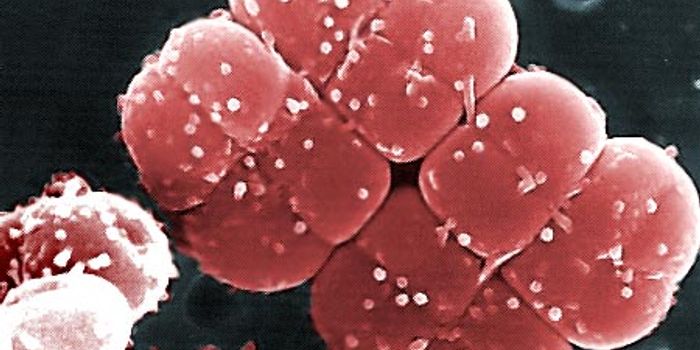

AUG 28, 2015MicrobiologyAs of 2012, roughly 35 million people were living with HIV worldwide, and 1.5 million died from AIDS-related illnesses i ...